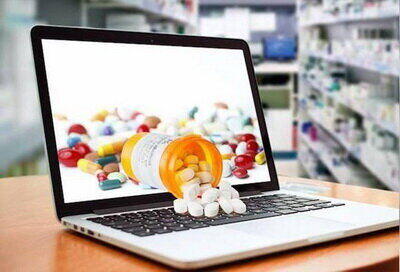

خطر خرید دارو از اینترنت!

ملیحه محمودخواه-خبرنگار گروه جامعه: با گسترش فناوریهای دیجیتال و افزایش استفاده از اینترنت، فروش دارو از طریق سکوهای اینترنتی (پلتفرمهای آنلاین) به یکی از روشهای رایج خرید دارو تبدیل شده است. این روش اگرچه مزایایی مانند دسترسی آسان، صرفهجویی در زمان و تنوع محصولات را به همراه دارد اما چالشها و مشکلات …

قلدری پلتفرمها و فروش اینترنتی دارو

فروش و عرضهی اینترنتی دارو، از چند سال پیش به چالش بزرگ وزارت بهداشت و سازمان غذا و دارو تبدیل شده است.

۱۴۰۳/۰۳/۱۶ / سایت اقتصاد ایران

طرح فروش اینترنتی دارو کلید خورد

رئیس مرکز بهبود محیط کسب و کار گفت: مجوز فعالیت پلتفرم های فروش دارو در هئیت مقررات زدایی تصویب و صادر شده است. رئیس مرکز

۱۴۰۳/۰۳/۰۷ / خبرگزاری همشهریآنلاین

درخواست کسب و کارهای اینترنتی برای اعلام عمومی آییننامه توزیع آنلاین دارو

کسب و کارهای اینترنتی در اظهارنامه ای از وزرای بهداشت و ارتباطات خواستهاند براساس تکالیف قانونی خود، در مدت یک هفته آییننامه حمل و عرضه دارو از طریق پلتفرمها و کسب و کارهای اینترنتی را اعلام عمومی کنند.